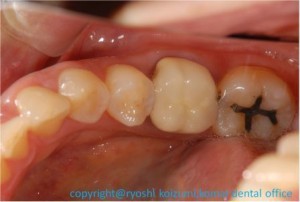

図1 左下の奥歯2本に問題あり

この方は、左下の奥歯のうち、1本は古いセラミック冠が、

一番奥はアマルガムという銀が詰めてありましたが、

違和感がする、ということでレントゲンを撮影したところ、

冠の歯は根の先に膿がたまってるようでした。銀の入った歯は

むし歯が見つかりました。